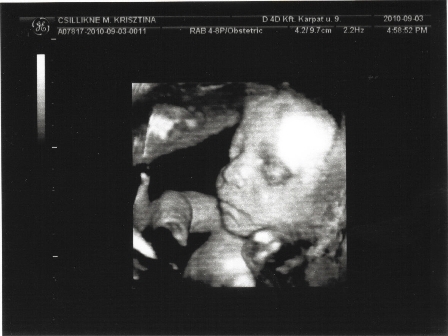

Bár már van 3 gyerkőcöm,de még sosem voltunk ezelőtt 4D-n (megmondom őszintén,nem nagyon izgatott régebben a dolog), nekem ezért olyan "nagy cucc" ez most!